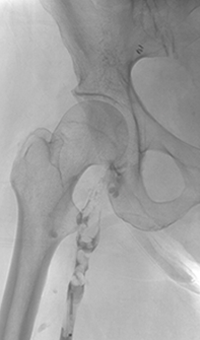

Thrombectomy of Occluded SFA - pre-procedure

Imaging SFA showing thrombus and calcification

Male in his late 40s presenting with pain in his right leg. An angiogram showed a total occlusion in the right superior femoral artery (SFA)